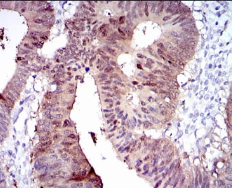

CYP1A1 Mouse Monoclonal antibody[6G5D]

This gene, CYP1A1, encodes a member of the cytochrome P450 superfamily of enzymes. The cytochrome P450 proteins are monooxygenases which catalyze many reactions involved in drug metabolism and synthesis of cholesterol, steroids and other lipids. This protein localizes to the endoplasmic reticulum and its expression is induced by some polycyclic aromatic hydrocarbons (PAHs), some of which are found in cigarette smoke. The enzyme's endogenous substrate is unknown; however, it is able to metabolize some PAHs to carcinogenic intermediates. The gene has been associated with lung cancer risk. A related family member, CYP1A2, is located approximately 25 kb away from CYP1A1 on chromosome 15.

IHC    1/200 - 1/1000